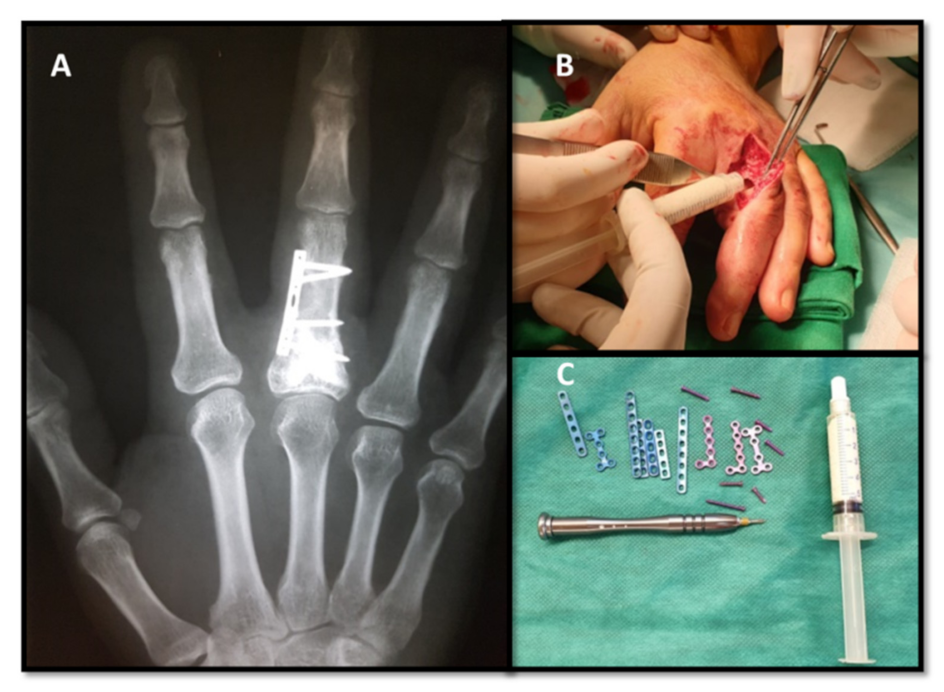

Enchondroma Hand

Enchondroma - Azouz Hand SurgeryAzouz Hand Surgery Enchondromas - Pathology - Orthobullets LearningRadiology- Enchondroma Enchondroma-of-hand LearningRadiology- Enchondroma Enchondroma Hand